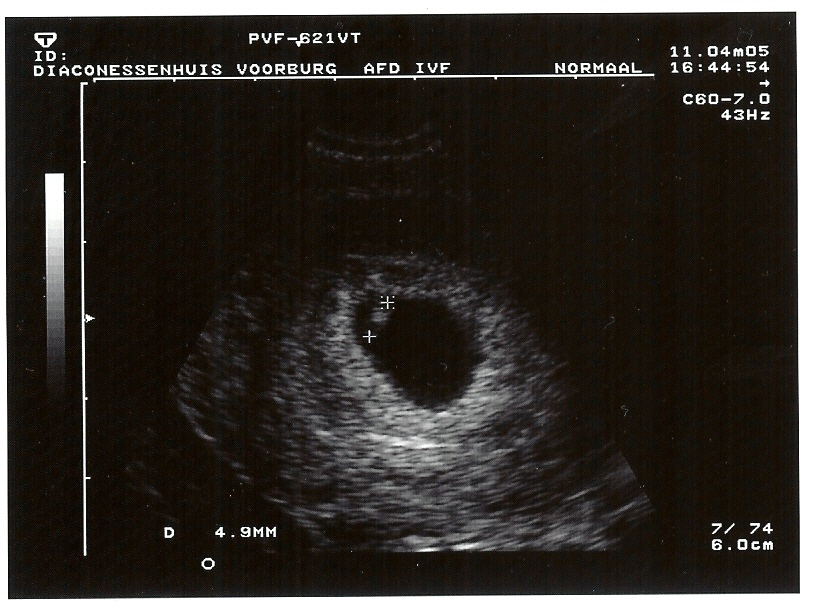

11-4-2005 Charmain 6 weken, 4 dagen, 4.9mm